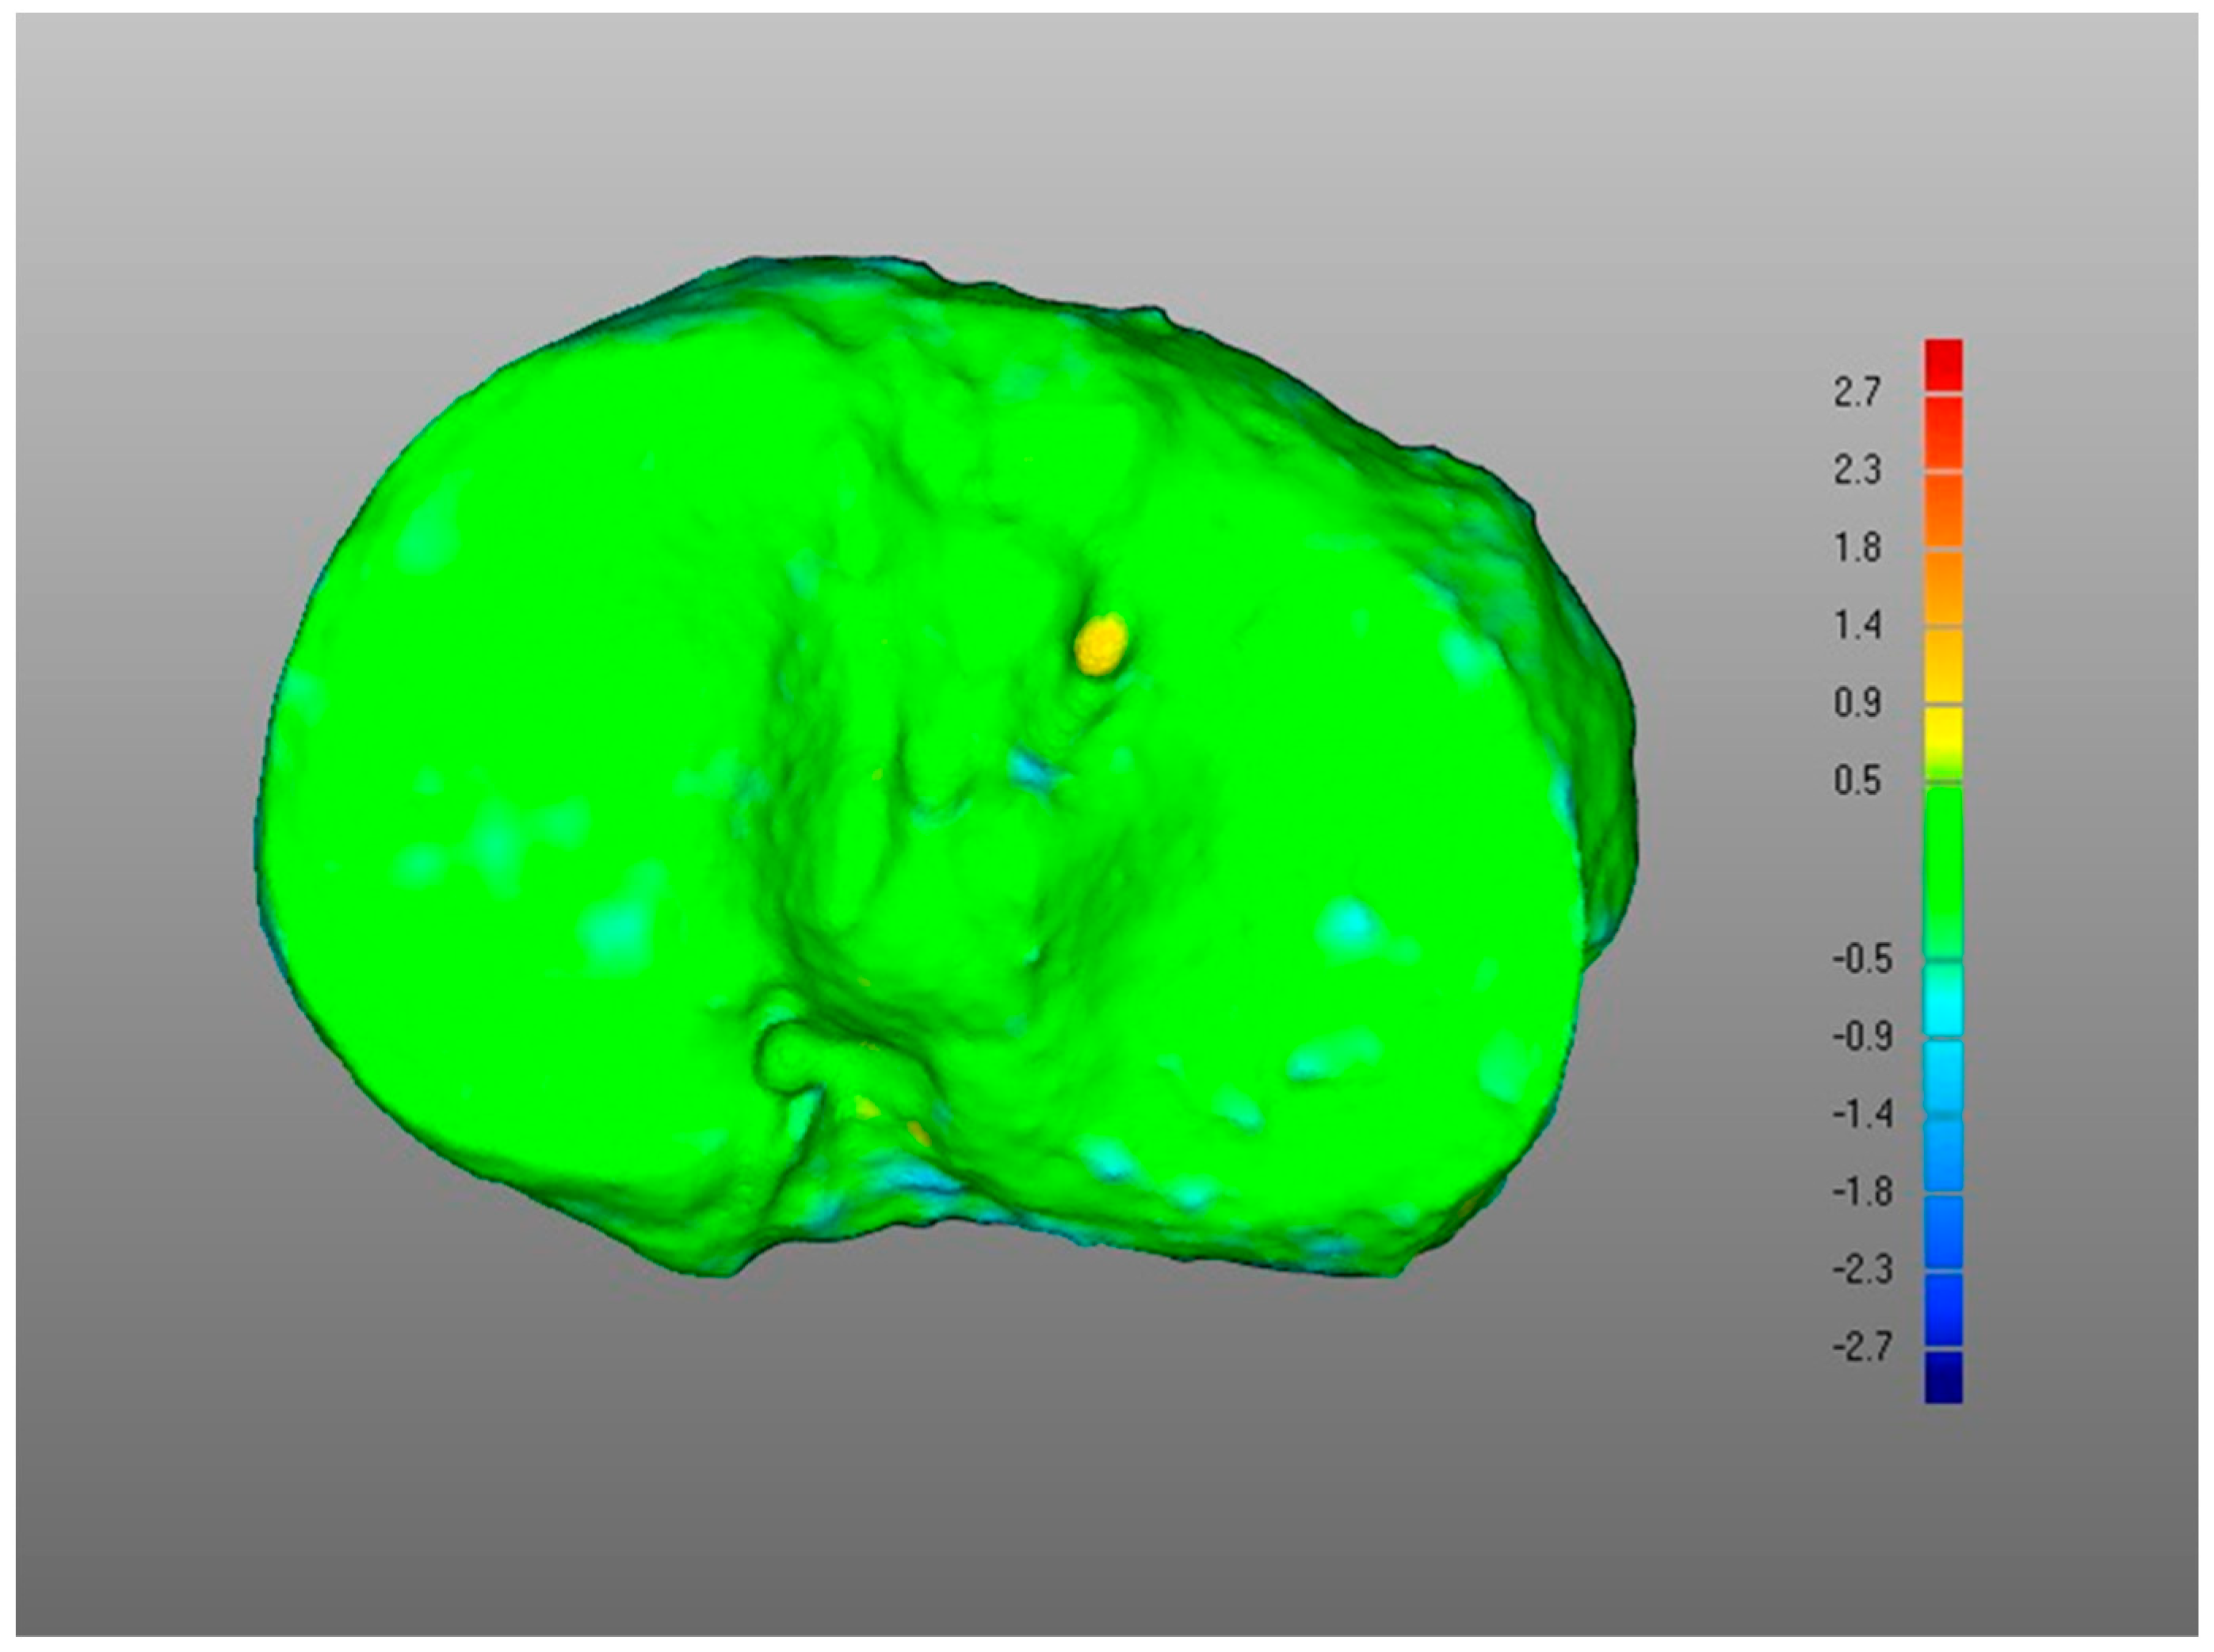

DMA Comparison Variable Mean Median Standard Deviation (i) POST tibia vs. PLA tibia 1.4 1.4 0.5 −0.9 −0.8 0.4 DSD 1.6 1.4 0.5 (ii) POST plate vs. PLA plate 0.4 0.4 0.1 −0.2 −0.2 0.1 DSD 0.4 0.4 0.1 (iii-a) PLA plate vs. PLA tibia 1.3 1.3 0.2 0 0 0 DSD 0.5 0.4 0.2 (iii-b) POST plate vs. POST tibia 0.7 0.6 0.4 −0.3 −0.3 0.2 DSD 0.6 0.5 0.2 (iv) POST tib plateau vs. PRE tib plateau 0.4 0.4 0.2 −0.3 −0.2 0.1 DSD 0.6 0.6 0.2 Figure 3. Boxplots for positive mean distance (), negative mean distance (), and DMA standard deviation (DSD) for all sets of surface comparisons.Figure 3. Boxplots for positive mean distance (), negative mean distance (), and DMA standard deviation (DSD) for all sets of surface comparisons.Figure 4. Screenshot of DMA software depicting (i) POST tibia versus PLA tibia. Data from a representative case, the colour scale gives surface deviation in millimetres.Figure 4. Screenshot of DMA software depicting (i) POST tibia versus PLA tibia. Data from a representative case, the colour scale gives surface deviation in millimetres. - (ii)